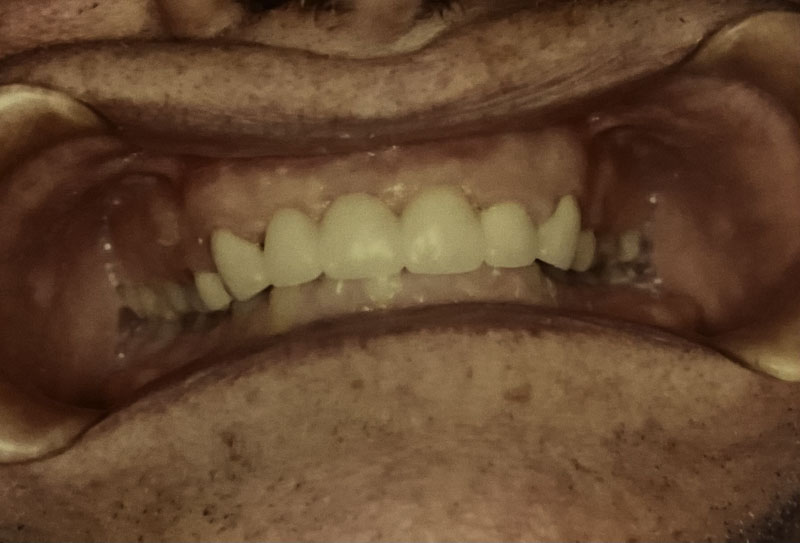

Before

After

Custom Cosmetic Crowns

Case Highlight